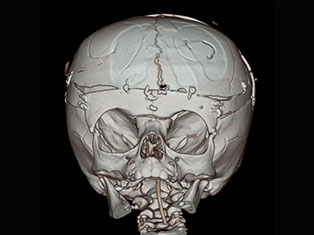

Brain Tumors

A brain tumor is a mass or growth of abnormal cells in your brain. Many different types of brain tumors exist. Some brain tumors are noncancerous (benign), and some brain tumors are cancerous (malignant).